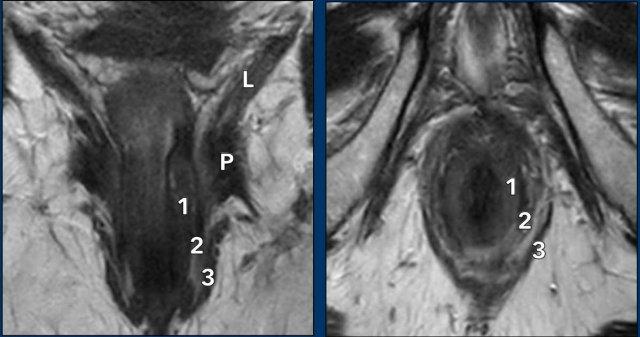

- Cơ thắt trong (1) thường có tín hiệu trung gian đến thấp trên chuỗi xung T2W MRI.

- Khoang liên cơ thắt chứa mỡ (2) có tín hiệu cao.

- Các lớp cơ vân của cơ thắt ngoài (3), cơ mu-trực tràng (P) và cơ nâng hậu môn (LA) có tín hiệu thấp.

Khi mô tả sự xâm lấn của cơ thắt trong và cơ thắt ngoài hậu môn, cần mô tả cả mức độ lan rộng theo chiều đầu-đuôi (ví dụ: nửa trên, nửa dưới hoặc toàn bộ chiều dài ống hậu môn) cũng như mức độ xâm lấn theo chu vi (ví dụ: từ … đến … giờ).

Hình ảnh

Một khối u xâm lấn 2/3 dưới của ống hậu môn.

Khối u xâm lấn cơ thắt trong, khoang liên cơ thắt và cơ thắt ngoài từ khoảng 12 giờ đến 3 giờ.

Không có xâm lấn sàn chậu, trực tràng hoặc bờ hậu môn.